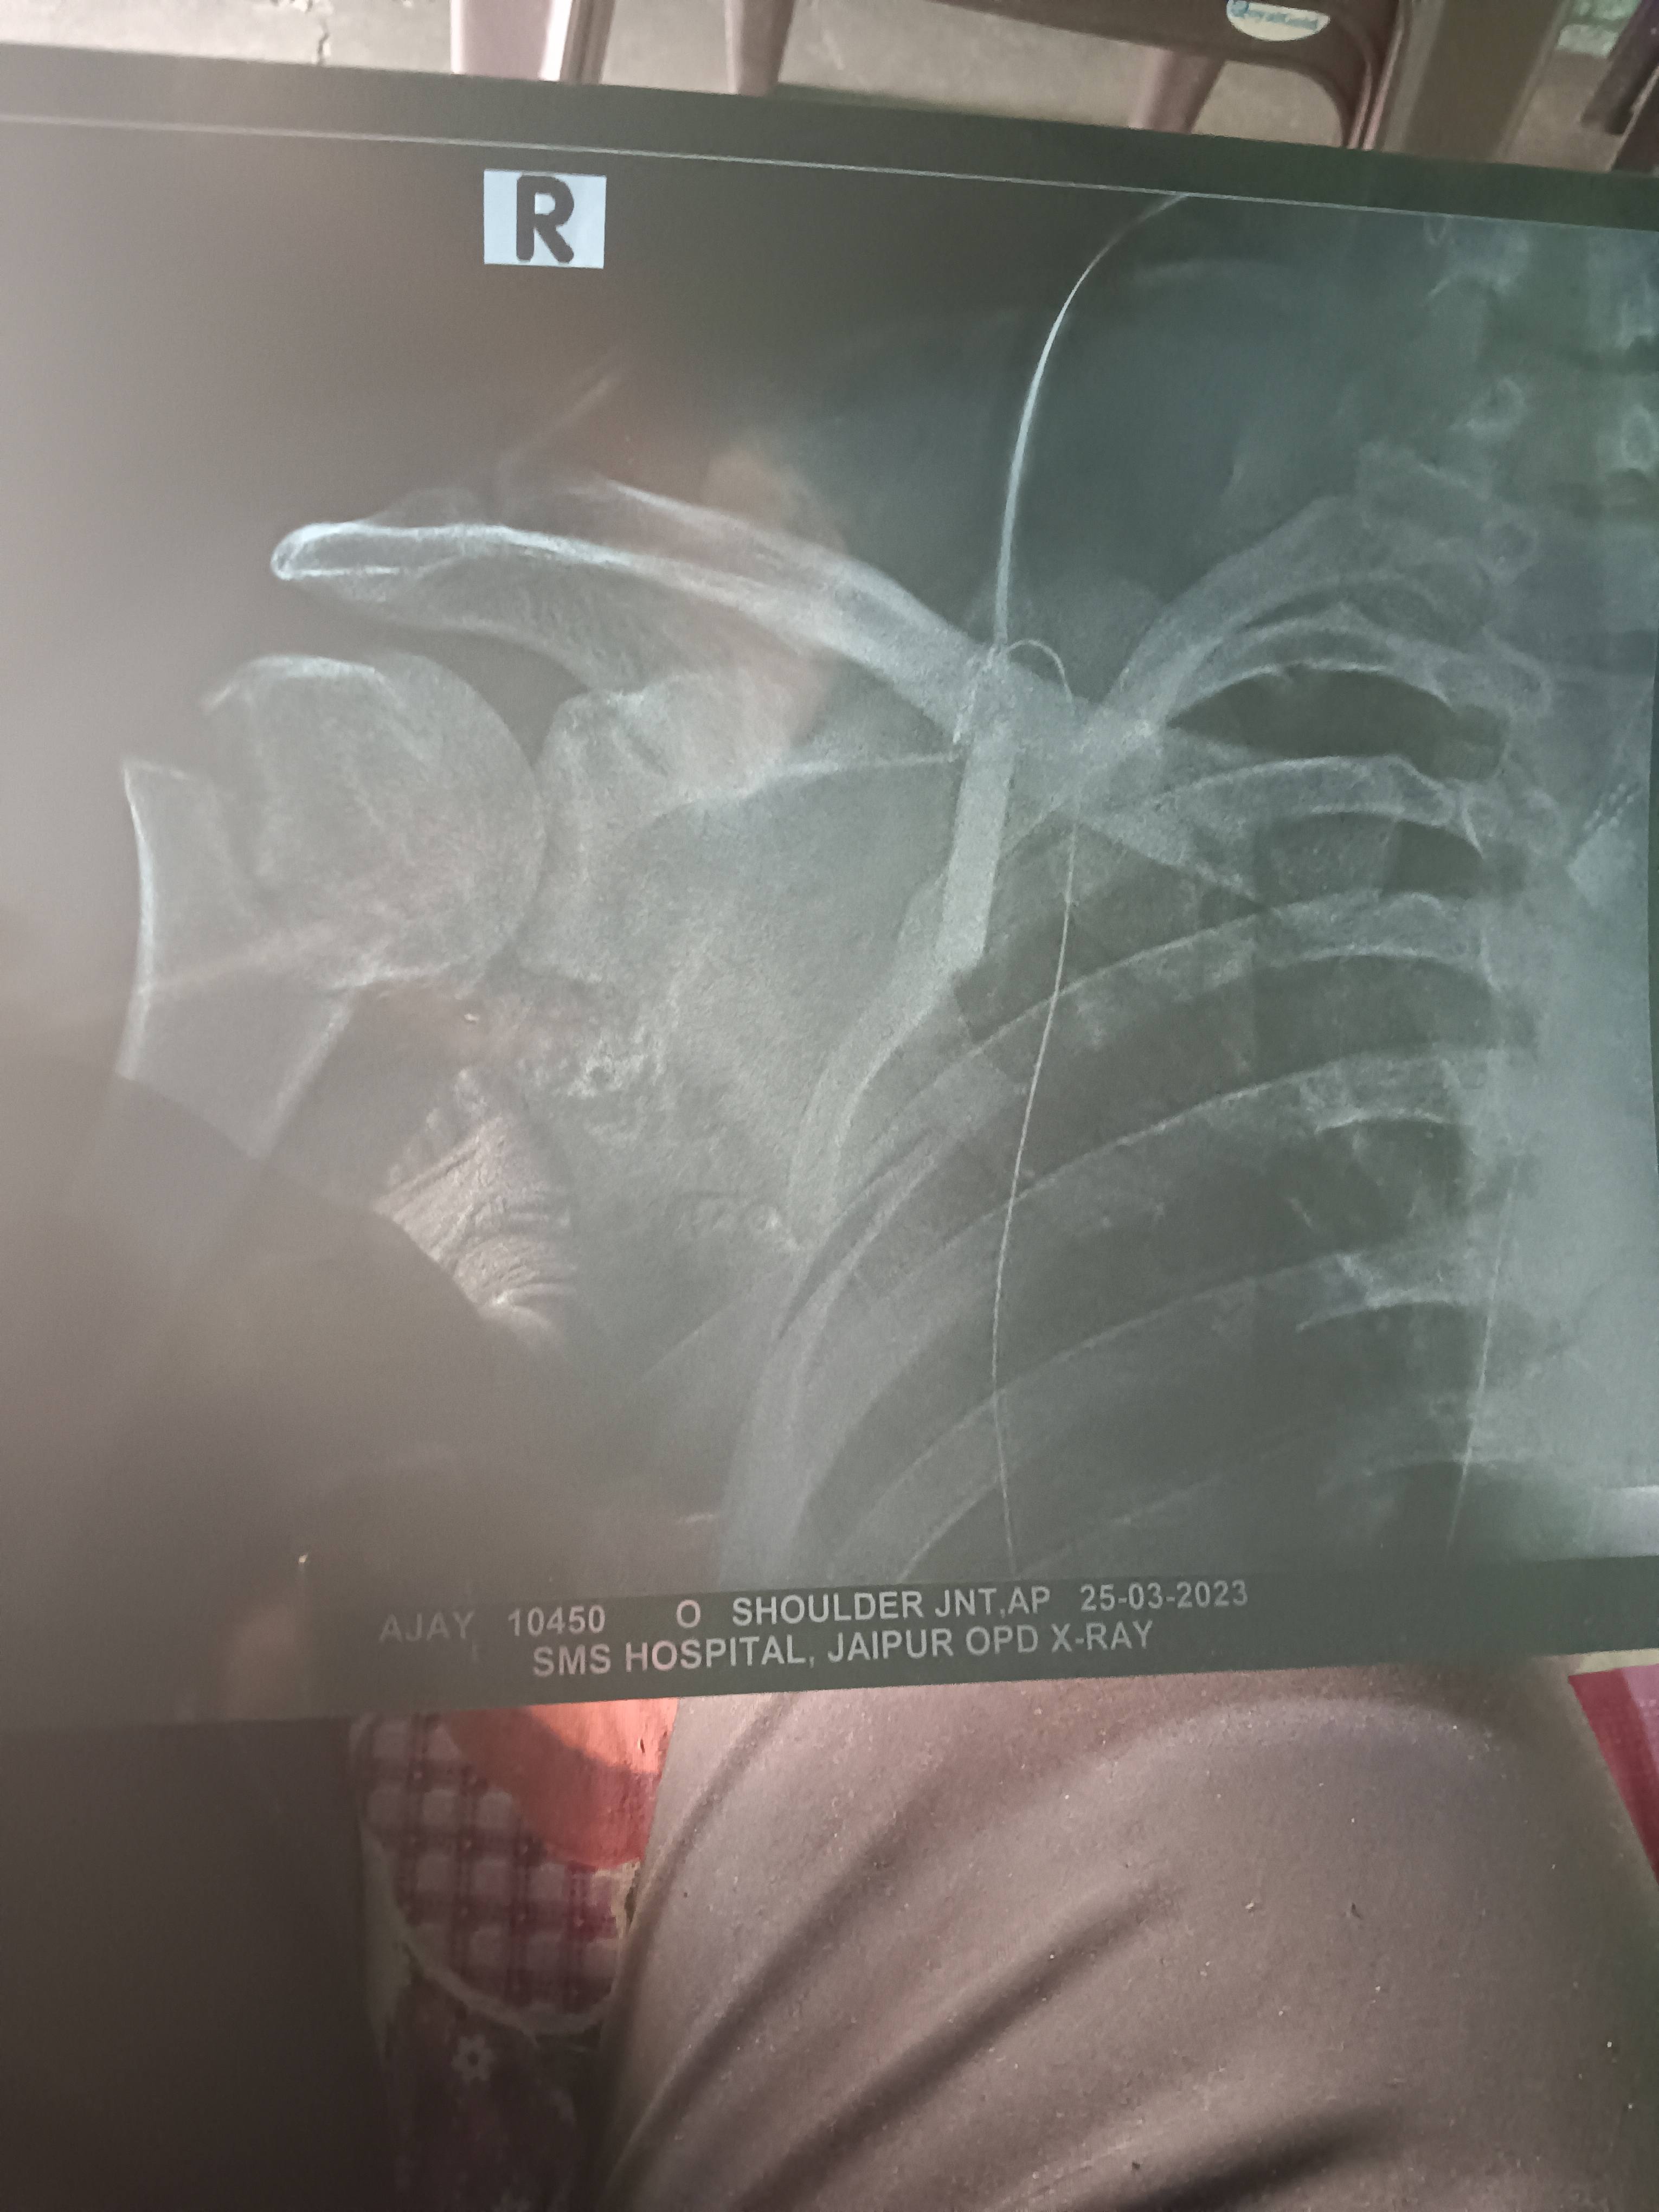

Sir Please solution